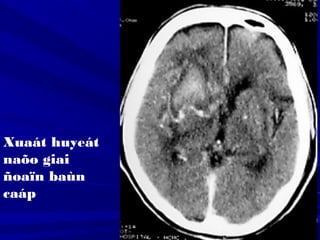

Xuaát huyeát

naõo giai

ñoaïn baùn

caáp

Fogging effect: Hiện tượng đồng đậm độFogging effect: Hiện tượng đồng đậm độ

vùng nhồi máu ở ngày 14-21 do tăng thựcvùng nhồi máu ở ngày 14-21 do tăng thực

bào hoặc xuất huyết vi thể, khi đó vùngbào hoặc xuất huyết vi thể, khi đó vùng

nhồi máu rất khó nhận thấy.nhồi máu rất khó nhận thấy.

Một số trường hợp có hiện tượng tăngMột số trường hợp có hiện tượng tăng

quang do xuất huyết trong vùng nhồi máuquang do xuất huyết trong vùng nhồi máu

vào sau ngày thứ ba.vào sau ngày thứ ba.